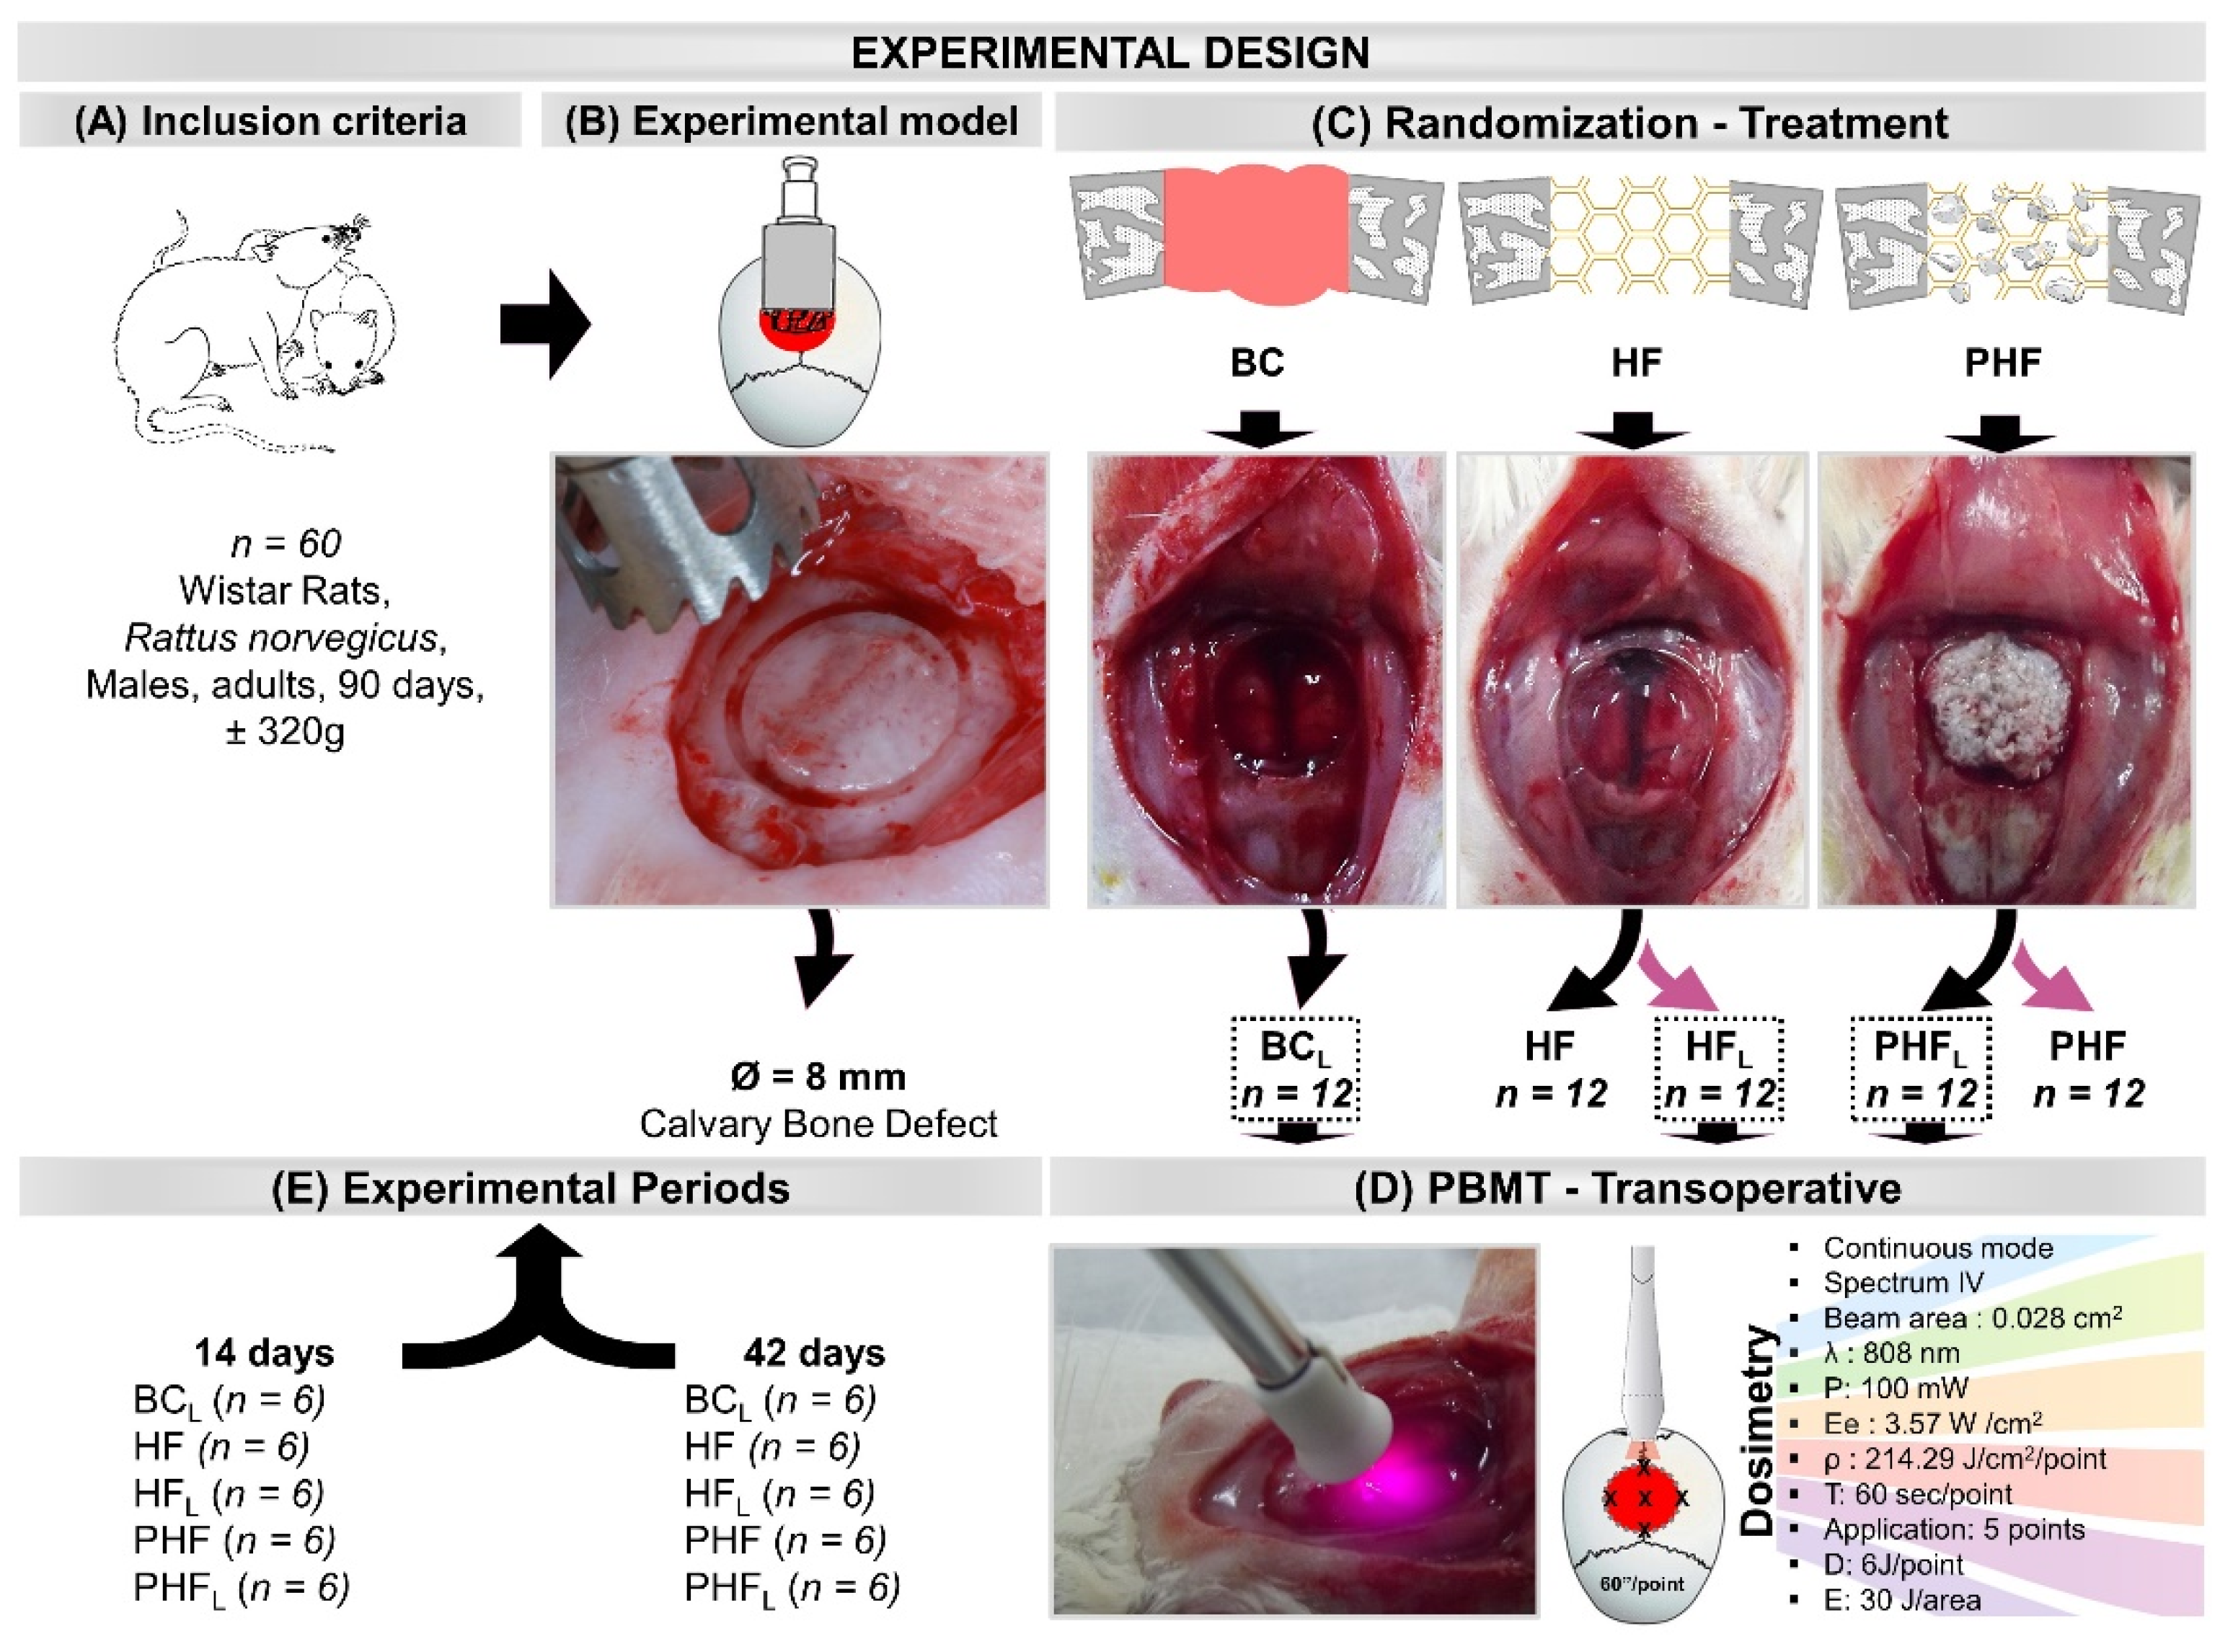

4. Materials and Methods

4.1. Deproteinized Bovine Bone Particles

4.2. Heterologous Fibrin Biopolymer

4.3. Selection and Maintenance of Animals

4.4. Experimental Procedure

4.5. Laser Photobiomodulation Therapy Protocol

4.6. Euthanasia and Tissue Collection

4.11. Statistical Analysis